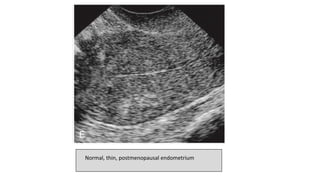

Normal, thin, postmenopausal endometrium

POSTMENOPAUSAL ENDOMETRIUM

• Postmenopausal Endometrium should be

thin, homogeneous, and echogenic.

• Homogeneous, smooth endometria

measuring 5 mm or less are considered

within the normal range with or without

hormonal replacement therapy.

• The endometrium in a patient

undergoing hormonal replacement

therapy may vary up to 3 mm if cyclic

estrogen and progestin therapy is being

used